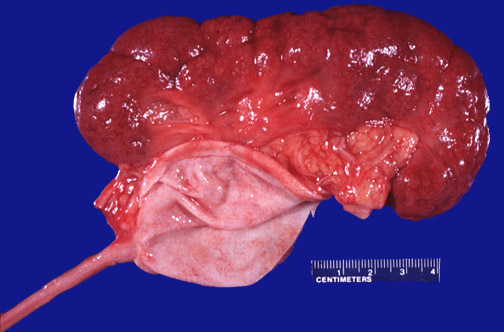

A 50 yo male non-smoker who recently moved from Cairo presents with hematuria and weight loss. Most likely diagnosis?

Squamous cell carcinoma of bladder associated with schistosoma haematobium

(Classic presentation according to Handorf; the oval things are the schistosoma??)